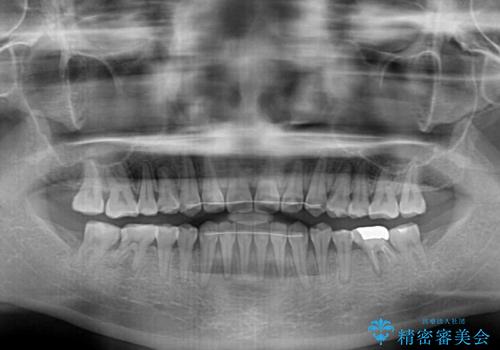

- 上下の前歯の隙間を気にして来院された患者様です。

インビザラインを用い、上下歯列のスペースを閉じていくこととしました。

治療期間中は奥歯がほとんど咬めない状態が続き、食事に大変苦労されました。

最終的には隙間もしっかりと閉じ、奥歯も咬みやすい状態でしあげることができました。